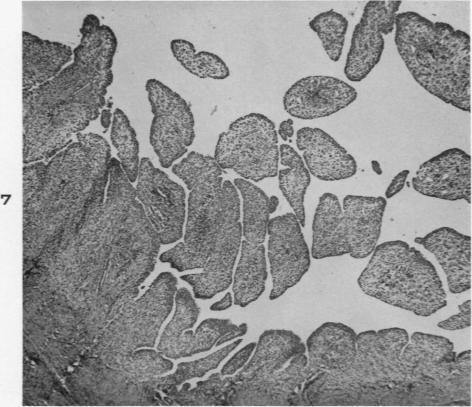

Experimental production of pigmented villonodular synovitis in dogs.

Am J Pathol. 1954 Jul-Aug;30(4):799-811.